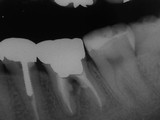

症例 4.

根管内に穿孔が2カ所あったケース

歯茎の腫脹及び咬むと痛みが出るため受診。スクリュウータイプの土台が根っこの内側の薄い部分に穿孔している。不注意な土台形成に起因している。

このような根っこが分岐している所での穿孔は予後が悪く治療難易度が非常に高い。

しかし、

マイクロスコープ

とMTA(修復材料)を使用することにより今までは抜歯になっていた症例もこのように抜かずに保存することが可能になった。

根っこが分岐している所に骨の再生が確認できる